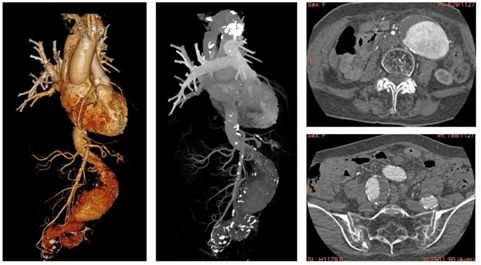

接诊的崔文军主任一触摸腹部,便判断很可能是“腹主动脉瘤”。随后的主动脉CTA检查证实了这一判断——刘奶奶的腹主动脉最粗处直径已达7厘米,一侧髂动脉也扩张至近4厘米,均处于破裂边缘!

▲ 术前胸腹主动脉CTA检查,腹主动脉巨大动脉瘤